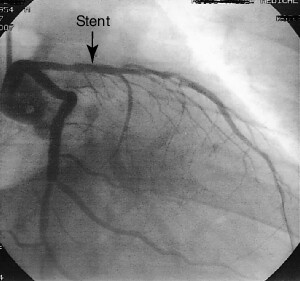

Angiography of the coronary arteries to determine any pathological obstructions to blood flow to the heart muscle. It is used to provide definitive images of the coronary arteries that reveal atherosclerotic blockage to blood flow so that those blockages can be surgically bypassed, opened, e.g., with angioplasty or stenting, or treated with medications.

CORONARY ANGIOGRAPHY A. tight stenosis; B. artery reopened with a stent